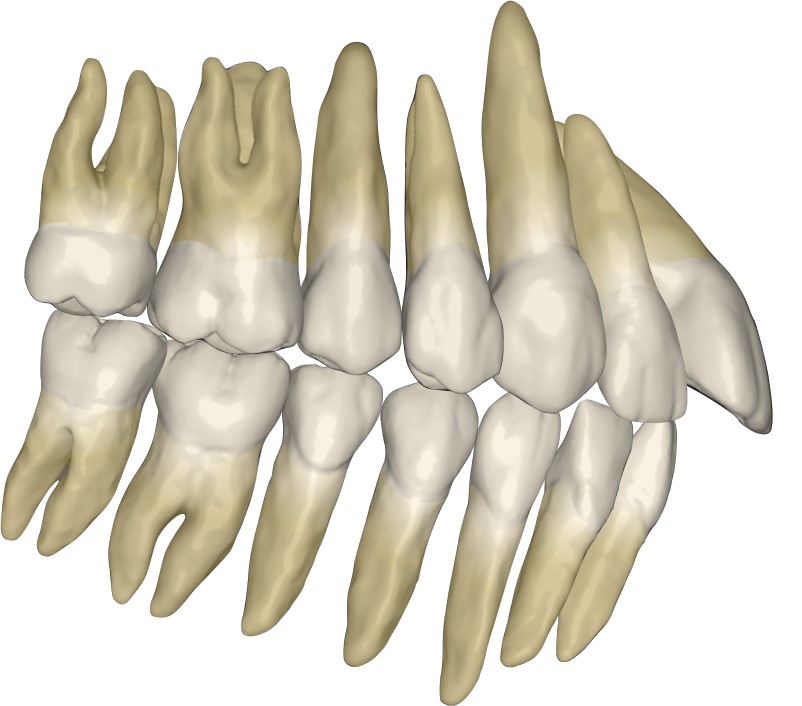

牙齿矢量图素材 | Keynote+PPT双平台可编辑 | 每颗牙独立图层 正畸教学必备

专业牙齿矢量图素材库,Keynote与PowerPoint双平台完美兼容!每颗牙齿独立图层设计,支持单独移动、缩放、改色,无需专业绘图软件,打开即用。包含完整牙列、单颗牙解剖图、咬合关系、正畸支抗示意图等20+模板,专为牙科教学、正畸方案演示、医学科普课件打造。

✅ 精细到每颗牙:32颗牙齿独立矢量图层,精准调整位置与形态

✅ 高清矢量无损缩放:适配手机端展示、大屏投影、印刷物料多种场景